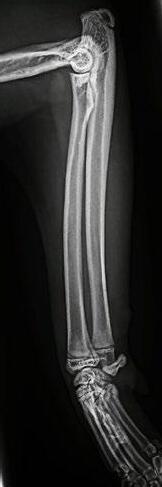

Tallulah presented as an 18-week-old Domestic Short Hair kitten with a persisting left forelimb lameness. On examination, she was uncomfortable on manipulation of the forelimb and painful on palpation over the left humerus. She was quiet and played for shorter time periods. She was in good body condition and eating well but had a temperature of 39.4° C. Radiographs suggested osteomyelitis of the left humerus, with extensive moth-eaten osteolysis of the diaphysis ( Figure 4).

She was given Amoxyclav (25mg/kg BID) and re-examined and radiographed 2 weeks later—by this time she was absolutely normal, with no pain or lameness and a normal temperature.

She is currently still on her antibiotics for 8 weeks before she is reviewed for repeat X-rays and spey!

3A 3B 4A 4B 3C

Figure 5. Lateral radiograph of the affected left leg (A) compared with the normal contralateral right leg (B) 2 weeks after stating amoxicillin clavulanate. Note the irregular areas of osteolysis of the left humerus are MUCH IMPROVED.

5A 6A 6B 5B

Figure 6. Lateral radiograph of the affected left leg (A) compared with the normal contralateral right leg (B) 8 weeks after stating amoxicillin clavulanate. Note the irregular areas of osteolysis of the left humerus are MUCH IMPROVED after extensive remodelling.